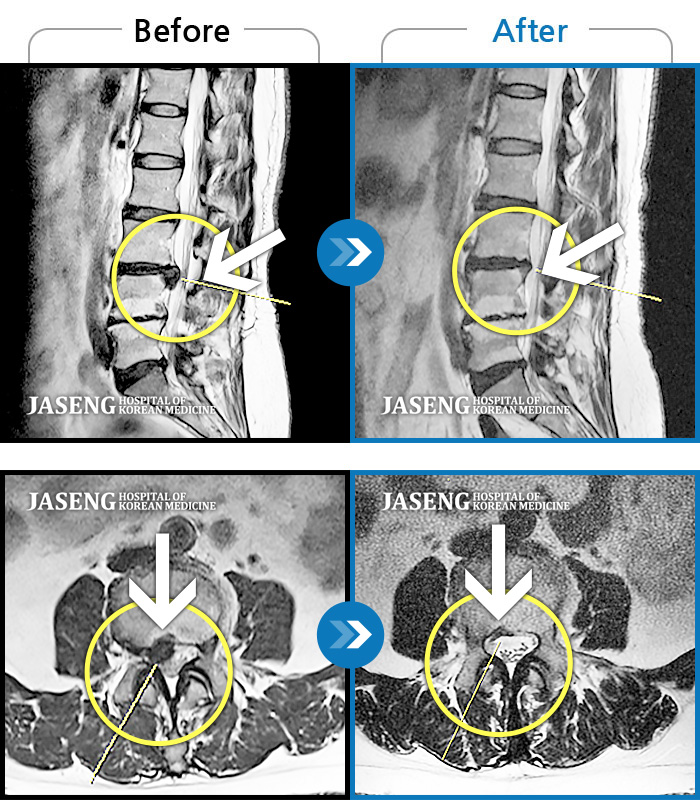

MRI 치료사례

허리 오른쪽에서 오른쪽 골반까지 찌르는 듯한 통증